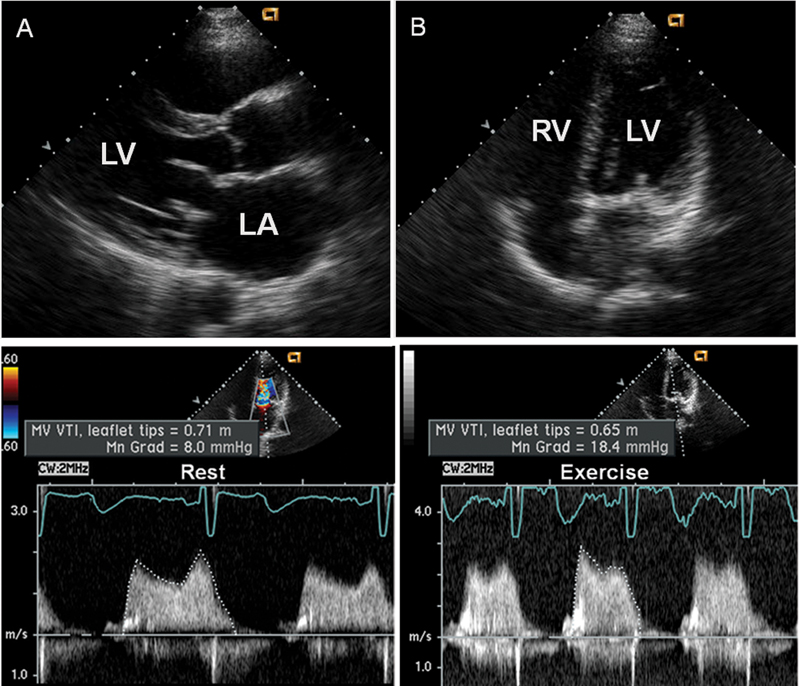

فحوصات تشخيصية لبعض امراض القلب والشرايين التاجية